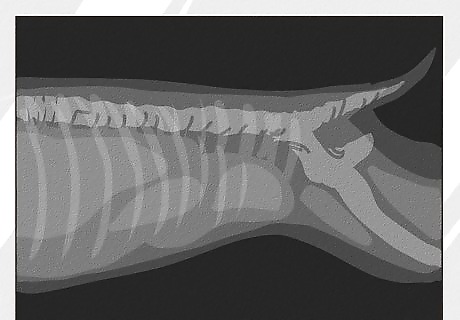

Have imaging done. It is often possible to identify the cause of infection, which could be urinary crystals, a bladder stone, a bladder polyp, or bladder cancer, with the help of imaging. Veterinary offices usually use either X-rays or ultrasounds, depending on what is available. X-rays of the dog's abdomen can help identify bladder stones. However, not all stones show up on x-ray, depending on their mineral composition. Thus, ultrasound is a better test. Ultrasounds can detect bladder stones no matter what their mineral composition. Bladder stones often create similar symptoms to bladder infections.